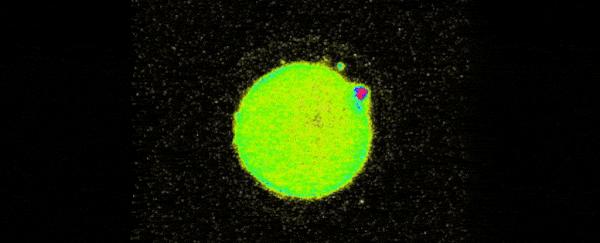

有不少人感到很困惑,这种闪光怎么被拍摄到的,你不会想到是把摄像头伸到体内里面去拍吧!其实从技术上来说,这个问题并不难解决,借助X射线荧光显微镜和电子显微镜,研究人员在卵细胞受精过程的培养基上就可以拍到这种闪光了。

卵细胞受精时的惊人闪光/美国西北大学

还有一点要值得大家注意,研究人员发现,受精胚胎的质量跟锌烟花的程度有关系。锌烟花越灿烂,受精胚胎的质量也就越高。因此,想孕育下一代的读者们,特别是女读者们要注意了,从现在开始,好好储备锌吧!